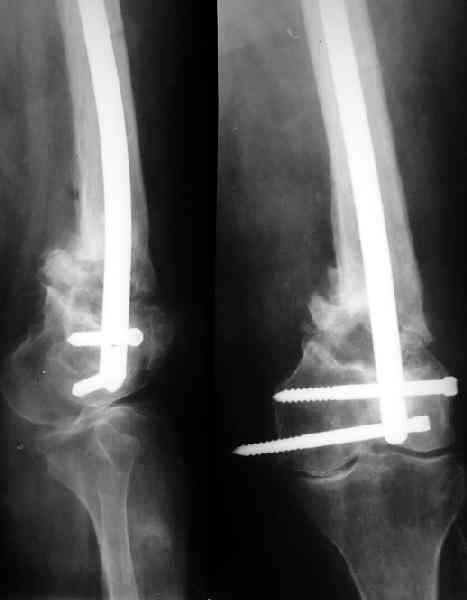

Доброго времени суток,уважаемые коллеги! Прошу вашего мнения. Больная, 53 лет,поступила с диагнозом: Ложный сустав н/3 бедренной кости слева. Травма в 1995г. Закрытый перелом н/3 левого бедра,лечение скелетным вытяжением. 15 лет ходила без трости. В 1-2010 года, рефрактура левого бедра в н/3. Лечение консервативное, скелетное вытяжение 2,5 месяца. Выписана в полужестком туторе. На ногу не опиралась, передвигается при помощи костылей. Инвалид 3 гр. посттромбофлебитический синдром левой нижней конечности. По дуплексному сканированию сосудов нижних конечностей вены проходимы, только на голени подкожная вена "посттромбофлебитическая".Из сопутствующих: ГБ,ДУЗ 0ст.Ожирение 1 ст.Предлагается костная пластика одним из существующих методов, накостный синтез мыщелковой пластиной LSP (Synthez). Укорочение левой ноги 3,5 см. Есть опасение, что накостный синтез ограничит периостальную регенерацию, да и травматичность операции при сопутствующих заболеваниях опасна в плане осложнений. Хотелось бы узнать мнение о ЧКДО и интрамедуллярном синтезе у данной пациентки. Стоит ли сначала "срастить" перелом, а потом коррегировать длину конечности? Или это нужно делать сразу? Может быть вообще ничего не делать и разрешить нагрузку? Пробую приложить Rn-гр. и томогр. Извиняюсь за качество обработки. Спасибо. Надеюсь на ваше понимание.

Смещение по длине см на 3 видно на снимке. Удобно и нетравматично восстановить длину и устранить смещение по ширине аппаратом.

Пример подобного ложного сустава в приложении.